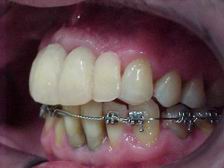

Provisórios estéticos guia anatômico VISTA LATERAL ESQUERDA

Provisórios estéticos (vista esquerda)